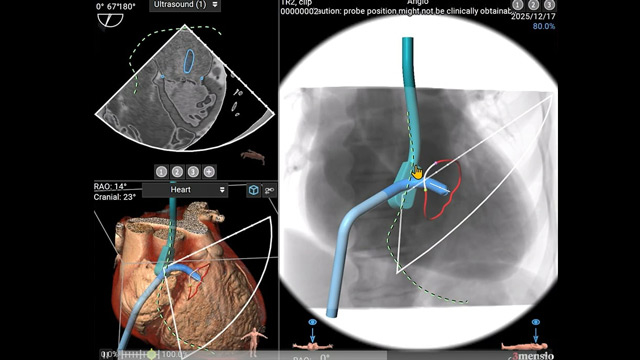

Mastering techniques from basic to complex - Mitral regurgitation assessment and suitability for TEER

13 Feb 2026 – From PCR Tokyo Valves 2026

Delve into the assessment of mitral regurgitation and the criteria determining suitability for Transcatheter Edge-to-Edge Repair (TEER). This session reviews mitral valve anatomy and the latest clinical data supporting mitral TEER interventions.